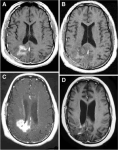

MRI US based thermocoagulation of tumors. [Neurosurgery – Current Table Of Contents] MRI guided ultrasound ablation of tumors, an experience from Israel with Zvi Ram reporting on 3 patients. Pre and Post ablation This is a technological tour de force, yet demonstrates how much further this technology needs to develop prior to widespread use. This evidences how technology will continue to drive neurosurgical practice.